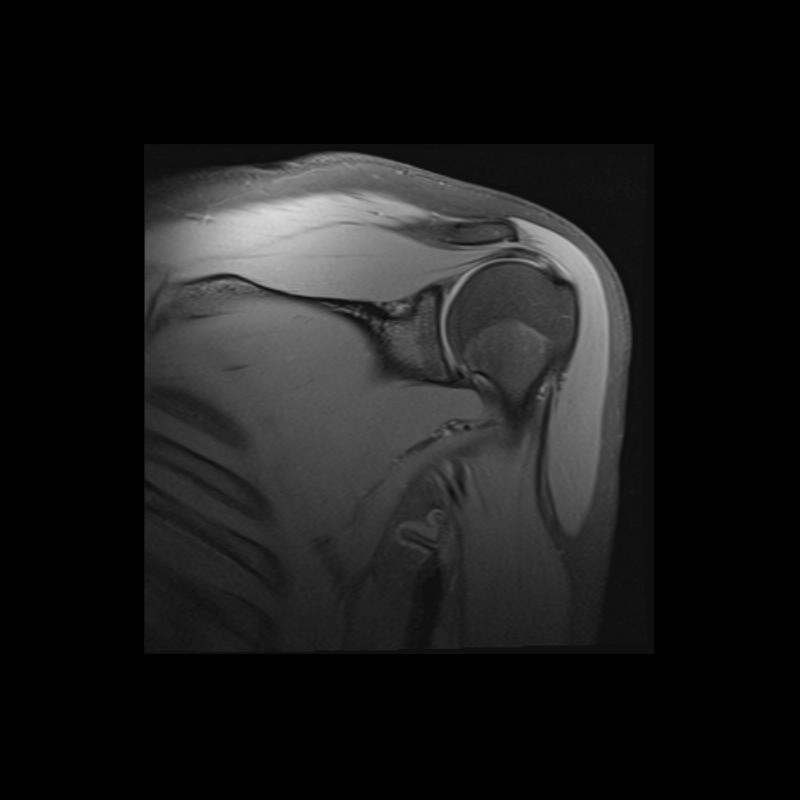

Shoulder MRI Anatomy